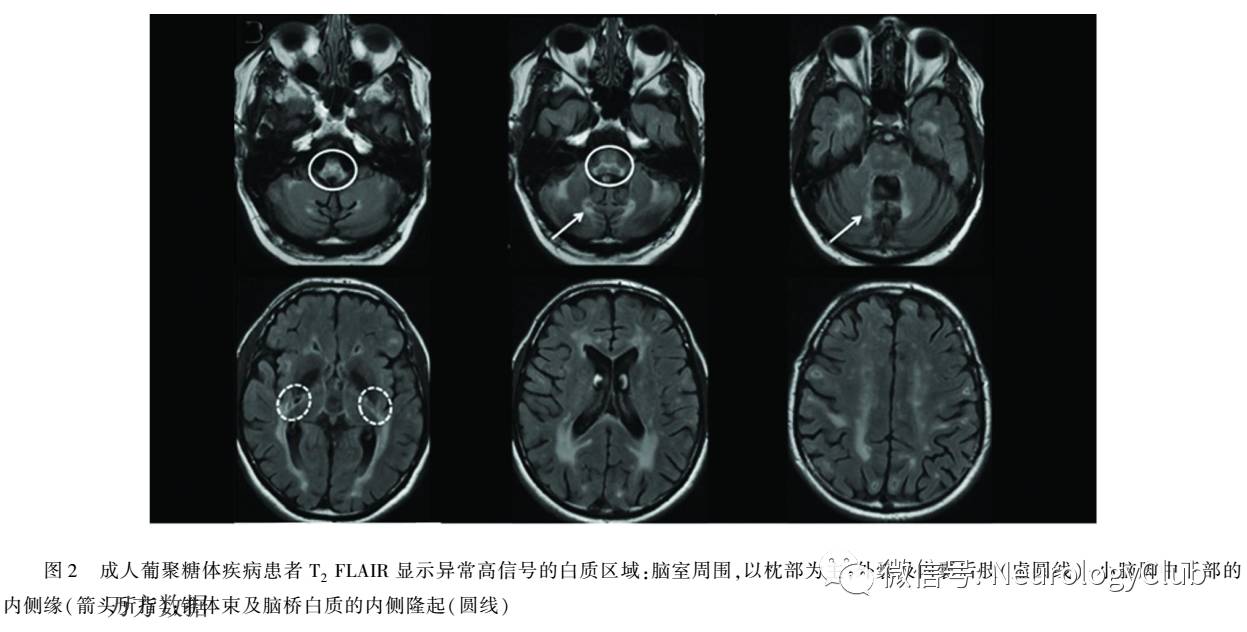

4.1 影像学检查  APBD患者往往具有非常相似的MRI表现,头部及脊髓的MRI表现主要包括:(1)脑部皮质及脊髓萎缩几乎存在于所有的患者中在大多数患者中,有不同程度的小脑蚓部和较不常见的半球萎缩,伴轻微的胼胝体变薄(见图1);(2)脑白质的异常改变,APBD患者的脑白质会出现异常高信号:一般在T2加权像和T2 FLAIR上出现,在T1加权像上为正常或低信号(见图2);白质病变部位一般对称出现,主要累及锥体束和大脑半球靠内侧部通常在脑室周围区域并且大部分在枕叶,颞叶也常累及;外囊和内囊的后肢常受影响,前肢常不受侵犯病灶融合或多灶,但通常两者同时存在(见图2)。

5.2 典型的头部及脊髓MRI  脑部皮质及脊髓的萎缩,主要累及锥体束及大脑半球内侧的脑白质的异常高信号影